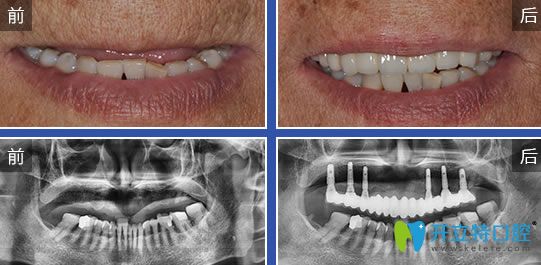

2、烤瓷牙種植前后對比案例圖: